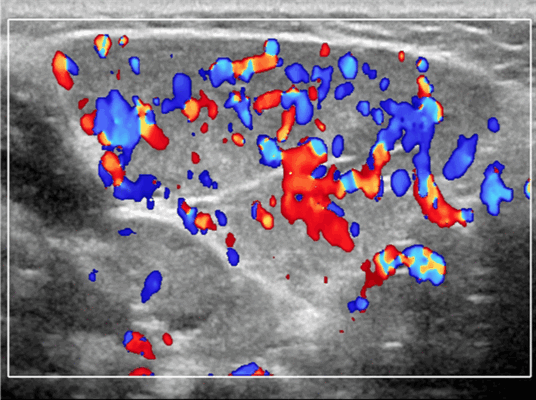

Энергетический допплер. Отмеченный доплеровский сигнал потока на всем протяжении пораженных сосудов

Результаты ультразвукового исследования. УЗИ в серошкальном режиме. Большинство сосудистых венозных гемангиом (80%) выглядят неоднородно гипоэхогенными. Большие анэхогенные сосудистые пространства видны менее чем в 50% случаев, серпигинозные и синусоидальные. Поражения с небольшими сосудистыми каналами могут казаться эхогенными (из-за множества акустических границ, отражающих звук). Определить пределы образования бывает трудно, так как компоненты поражения могут быть изоэхогенными в околоушной паренхиме и незаметно смешиваться. Внутрипросветное движение эхо-сигналов при УЗИ в реальном времени, представляющее медленный сосудистый кровоток. Характерны эхогенные флеболиты с задним акустическим затенением. Сообщается, что они присутствуют только в 20% ВСМ. Иногда поражается вся околоушная железа, имитируя диффузную или инфильтративную патологию. Целесообразность склеротерапии оценивается соотношением сосудистых пространств к эхогенной матрице

Импульсный допплер. Монофазный, низкоскоростной поток может иногда обнаруживаться в анэхогенных и гипоэхогенных пространствах, представляющих открытые сосуды со значительным кровотоком. Отсутствие допплеровского сигнала при медленном кровотоке или тромбировании

Цветной допплер. Выраженный цветной доплеровский сигнал присутствует в областях, где поток значительный. Используйте фильтр для стенок сосудов и низкую частоту повторения импульсов (PRF) для увеличения доплеровской чувствительности. Отсутствует допплеровский сигнал при медленном кровотоке или тромбировании. Доплеровский сигнал потока изменяется различными маневрами. В поверхностных участках доплеровский сигнал может быть остановлен прямым сжатием датчика над поражением. Сигнал потока может иногда быть усилен маневром Вальсальвы или дистальным сжатием, но последнее трудно выполнить в области лица.